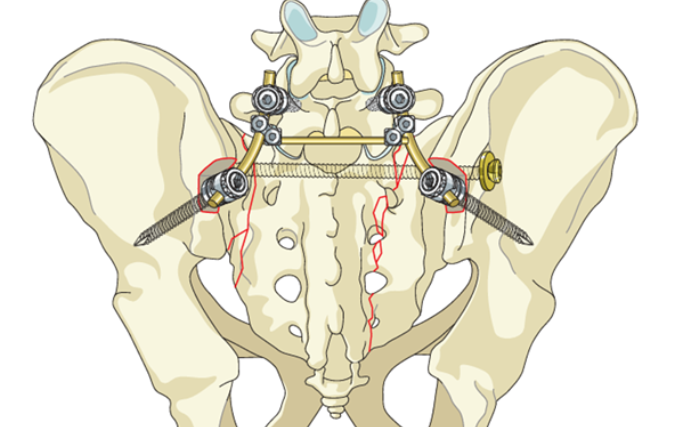

Çanaklygyň zeperlenmeleri we döwükleri

30

1